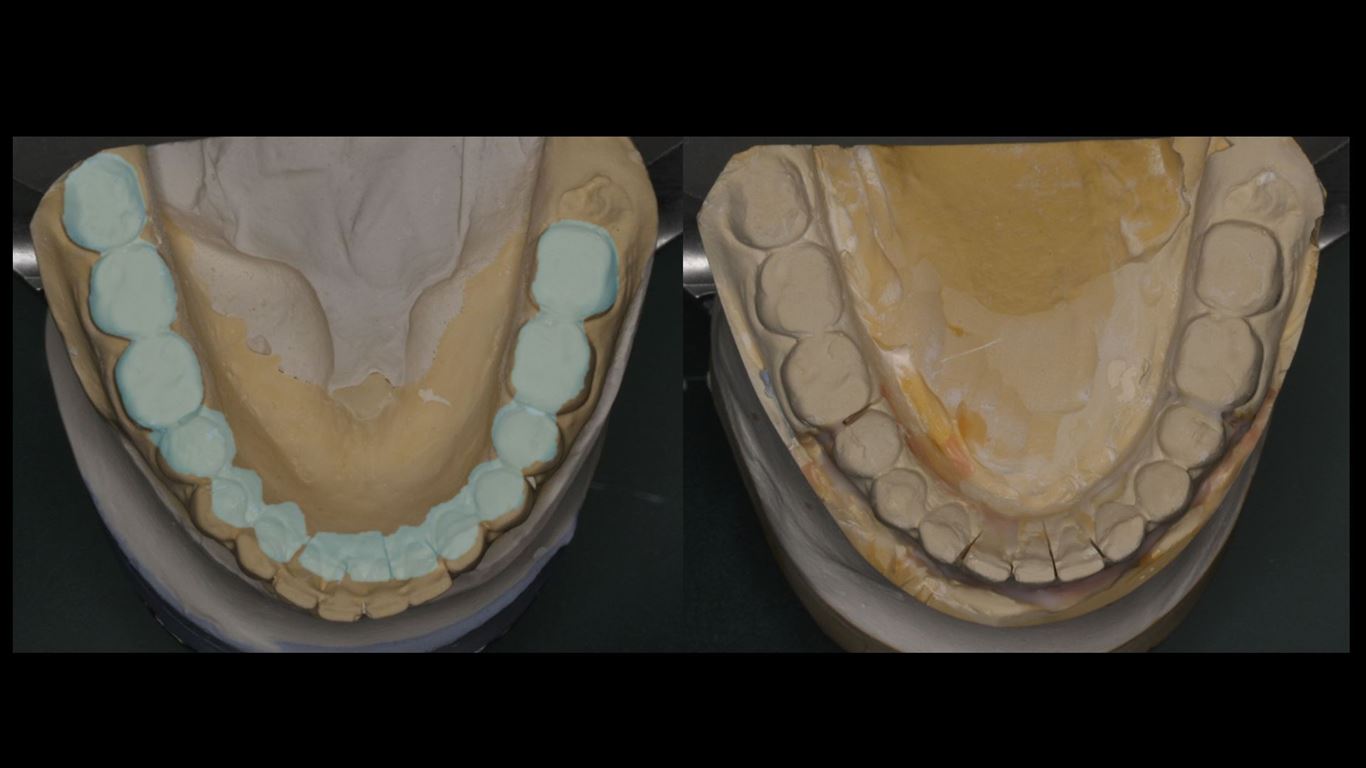

Następnie, po okresie stabilizacji i wstępnej korekcie okluzji, na podstawie analizy nowego kompletu zdjęć i modeli, wykonano woskowanie diagnostyczne oraz mock-up górnego łuku zębowego mający na celu potwierdzenie ostatecznego kształtu zębów i zakresu niezbędnego przygotowania chirurgicznego (ryc. 25-27).

Analiza fotografii z mock-upem potwierdziła konieczność wydłużenia koron klinicznych wszystkich zębów przednich o około 2 mm w kierunku dokoronowym oraz zębów 13-21 w kierunku dowierzchołkowym, w celu zharmonizowania poziomu zenitów dziąsłowych. W związku z tym w okolicy zębów 13-21 wykonano zabieg chirurgicznego wydłużania koron (ryc. 28, 29).

Po 6 miesiącach od zabiegu chirurgicznego rozpoczęto leczenie protetyczne mające na celu odbudowę prawidłowej anatomii zębów i odtworzenie utraconej funkcji żucia. W pierwszym etapie zaplanowano rekonstrukcję górnego łuku zębowego, wzorując się na wcześniej wykonanym woskowaniu i mock-upie. Preparacja przez mock-up pozwala na minimalnie traumatyczne szlifowanie, co jest szczególnie istotne w przypadkach takich jak przedstawiony, gdy już doszło do znacznej utraty tkanek na powierzchniach żujących zębów bocznych (16) (ryc. 30). Przed wykonaniem docelowych rekonstrukcji ceramicznych sprawdzono wyfrezowany z żywicy akrylopolimerowej (PMMA) prototyp z jednocześnie założonym na dolny łuk zębowy mock-upem (ryc. 31).